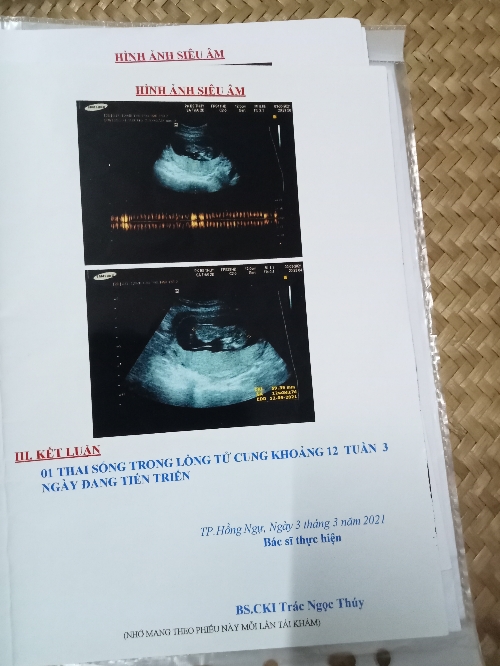

Dự kiến sinh của bạn lúc 12 tuần là ngày bao nhiêu?